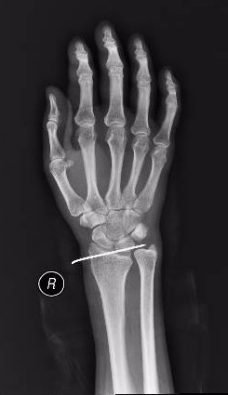

术后第一天,患者意识恢复清醒,复查头部CT提示颅内血肿清除彻底。全腹CT、双腕关节CT显示:肠管管壁明显水肿增厚,邻近肠系膜肿胀,肠间隙模糊,盆腔少量积液,腹腔内未见游离积气,提示肠管或肠系膜损伤;右侧月骨脱位,左侧桡骨远端骨折。

胃肠小儿外科、脊柱创伤外科会诊讨论,确定了分期治疗方案。术后第2天,胃肠小儿外科张达主任医师在全麻下为患者行小肠破裂修补术+腹腔脓肿清除术+肠粘连松解术+肠排列术。脊柱创伤外科薛建康主任医师为患者行左侧桡骨骨质手法复位后石膏外固定,后行右月骨脱位切开复位。

(左侧桡骨远端骨折) (手法复位及石膏外固定后位置良好)